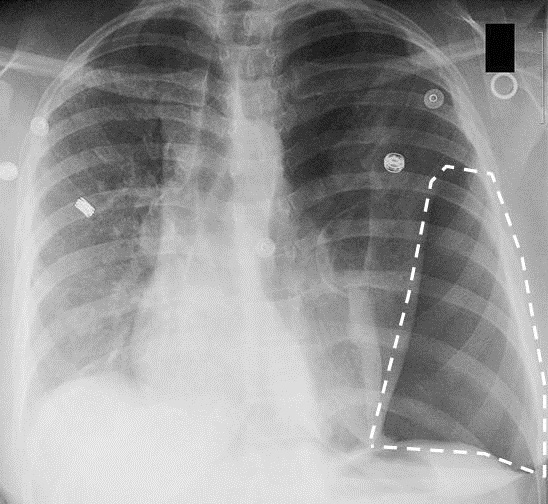

Después de la sorpresa inicial, se detiene a mirar la radiografía. ¿Qué puede ver en ella?